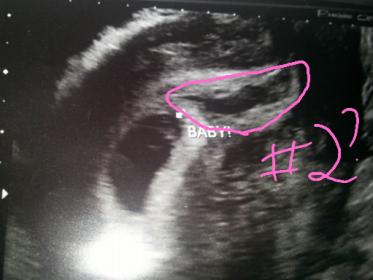

JUst curious if able to attempt ramzi and if anyone else send ad curious as I am about the black blob to the right? Have history of vanisHing twins so very curious. When did blood flow on baby it was to the right in the white part if that says anything also vaginal us. Please and thank you!